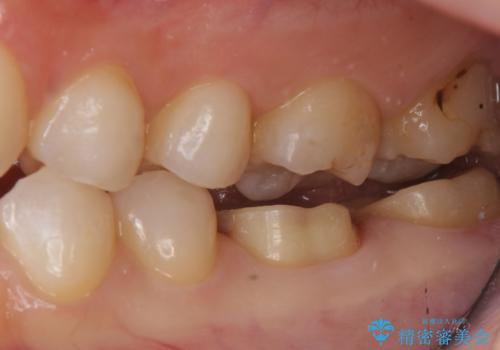

変色した樹脂の詰め物 セラミックでのやり替え

奥歯が樹脂の詰め物で継ぎ接ぎになっていることが確認されたため、今後の虫歯リスクを減らすために適合の良いフルジルコニアクラウンを入れていきます。

樹脂で継ぎ接ぎになった歯はそうでない歯と比べて虫歯になるリスクが高いです。

樹脂をすべて取り、虫歯も取り切った後に適合の良いクラウンを装着することで今後の虫歯リスクを減らすことができます。